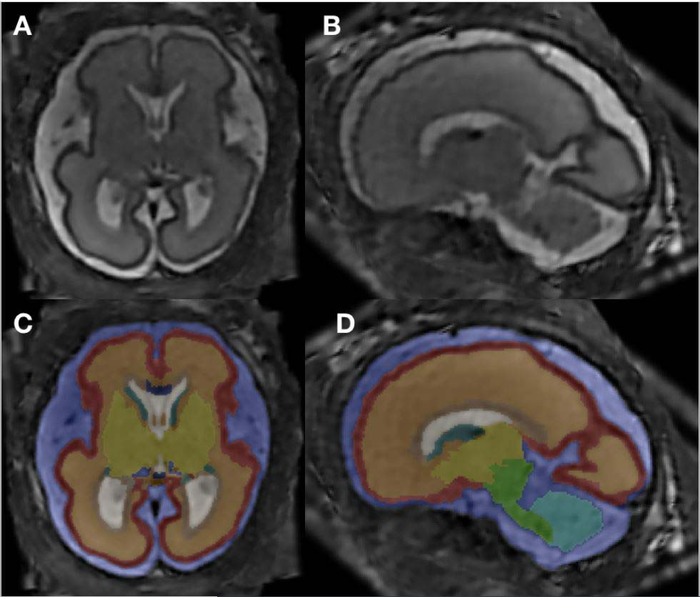

The researchers used super-resolution imaging, which allowed them to create one dataset to re-construct each fetal brain. Next, they completed an analysis of 12 different brain structures, computing total brain volume and segment volumes of specific brain compartments.

“One of the main hallmarks of our study is that we investigated so many smaller sub-compartments of the brain,” said co-author Marlene Stuempflen, M.D., scientific researcher at the Medical University of Vienna.

The statistical analysis revealed two major differences in the alcohol-exposed fetuses compared to healthy controls: an increased volume in the corpus collosum and a decreased volume in the periventricular zone.

The corpus collosum is the main connection between the brain’s two hemispheres. Dr. Stuempflen noted that it is fitting that this very central structure is affected, because the clinical symptoms of fetal alcohol spectrum disorders are highly heterogenous, or diverse, and cannot be pinpointed to one specific substructure of the brain.

“The changes found in the periventricular zone, where all neurons are born, also reflect a global effect on brain development and function,” she said.